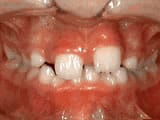

Open bite: front teeth don’t touch

Before

AfterThis girl sucked her thumb as a young child. She started treatment at age 13. She had braces and a special appliance — called a crib — to retrain the tongue, for 28 months. Now she can bite the lettuce out of a sandwich.